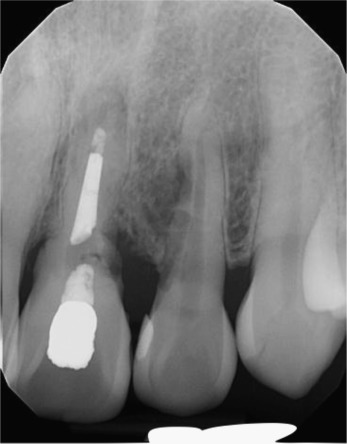

Fig. 2.

Pre-operative periapical radiograph showing external root resorption of maxillary left central and lateral incisors.